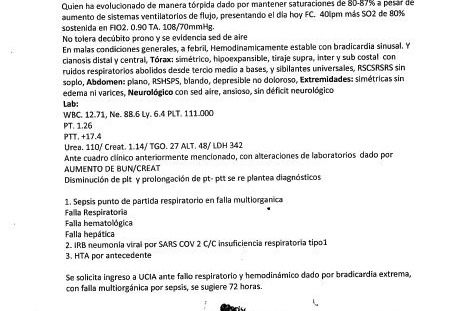

El 31 de agosto mi padre fue diagnosticado con neumonía bilateral vinculada al Covid-19. Si bien le aplicamos el tratamiento en casa, el lunes 14 tuvo que ser hospitalizado porque la infección respiratoria no cedía. Ahora, el médico tratante recomienda 5 días de terapia intensiva ante fallo respiratorio y hemodinámico, por bradicardia extrema, con falla multiorgánica por sepsis.

On August 31, my father was diagnosed with bilateral pneumonia linked to Covid-19. Although we applied the treatment at home, on Monday the 14th he had to be hospitalized because the respiratory infection did not subside. Now, the treating physician recommends 5 days of intensive therapy for respiratory and hemodynamic failure, for extreme bradycardia, with multiorgan failure due to sepsis.

El 31 de agosto mi padre fue diagnosticado con neumonía bilateral vinculada al Covid-19. Si bien le aplicamos el tratamiento en casa, el lunes 14 tuvo que ser hospitalizado porque la infección respiratoria no cedía. Ahora, el médico tratante recomienda 5 días de terapia intensiva ante fallo respiratorio y hemodinámico, por bradicardia extrema, con falla multiorgánica por sepsis.

On August 31, my father was diagnosed with bilateral pneumonia linked to Covid-19. Although we applied the treatment at home, on Monday the 14th he had to be hospitalized because the respiratory infection did not subside. Now, the treating physician recommends 5 days of intensive therapy for respiratory and hemodynamic failure, for extreme bradycardia, with multiorgan failure due to sepsis.